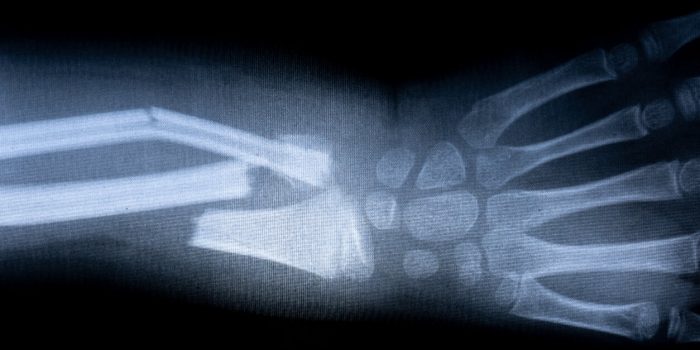

有一天,去医院治疗严重骨折可能不会导致骨置换手术或药物治疗,因为独特的材料,造骨微型机器人最终可能会提供一个不那么严重的替代方案。

研究人员对骨骼修复特别感兴趣。这种柔软的物质在电活性聚合物的推动下,可以移动并填充骨折中的空间。当材料变硬后,可以用来形成新的骨骼。研究表明,这种材料可以把自己包裹在鸡骨头周围,结果,出现的人造骨头就在鸡骨头旁边生长。